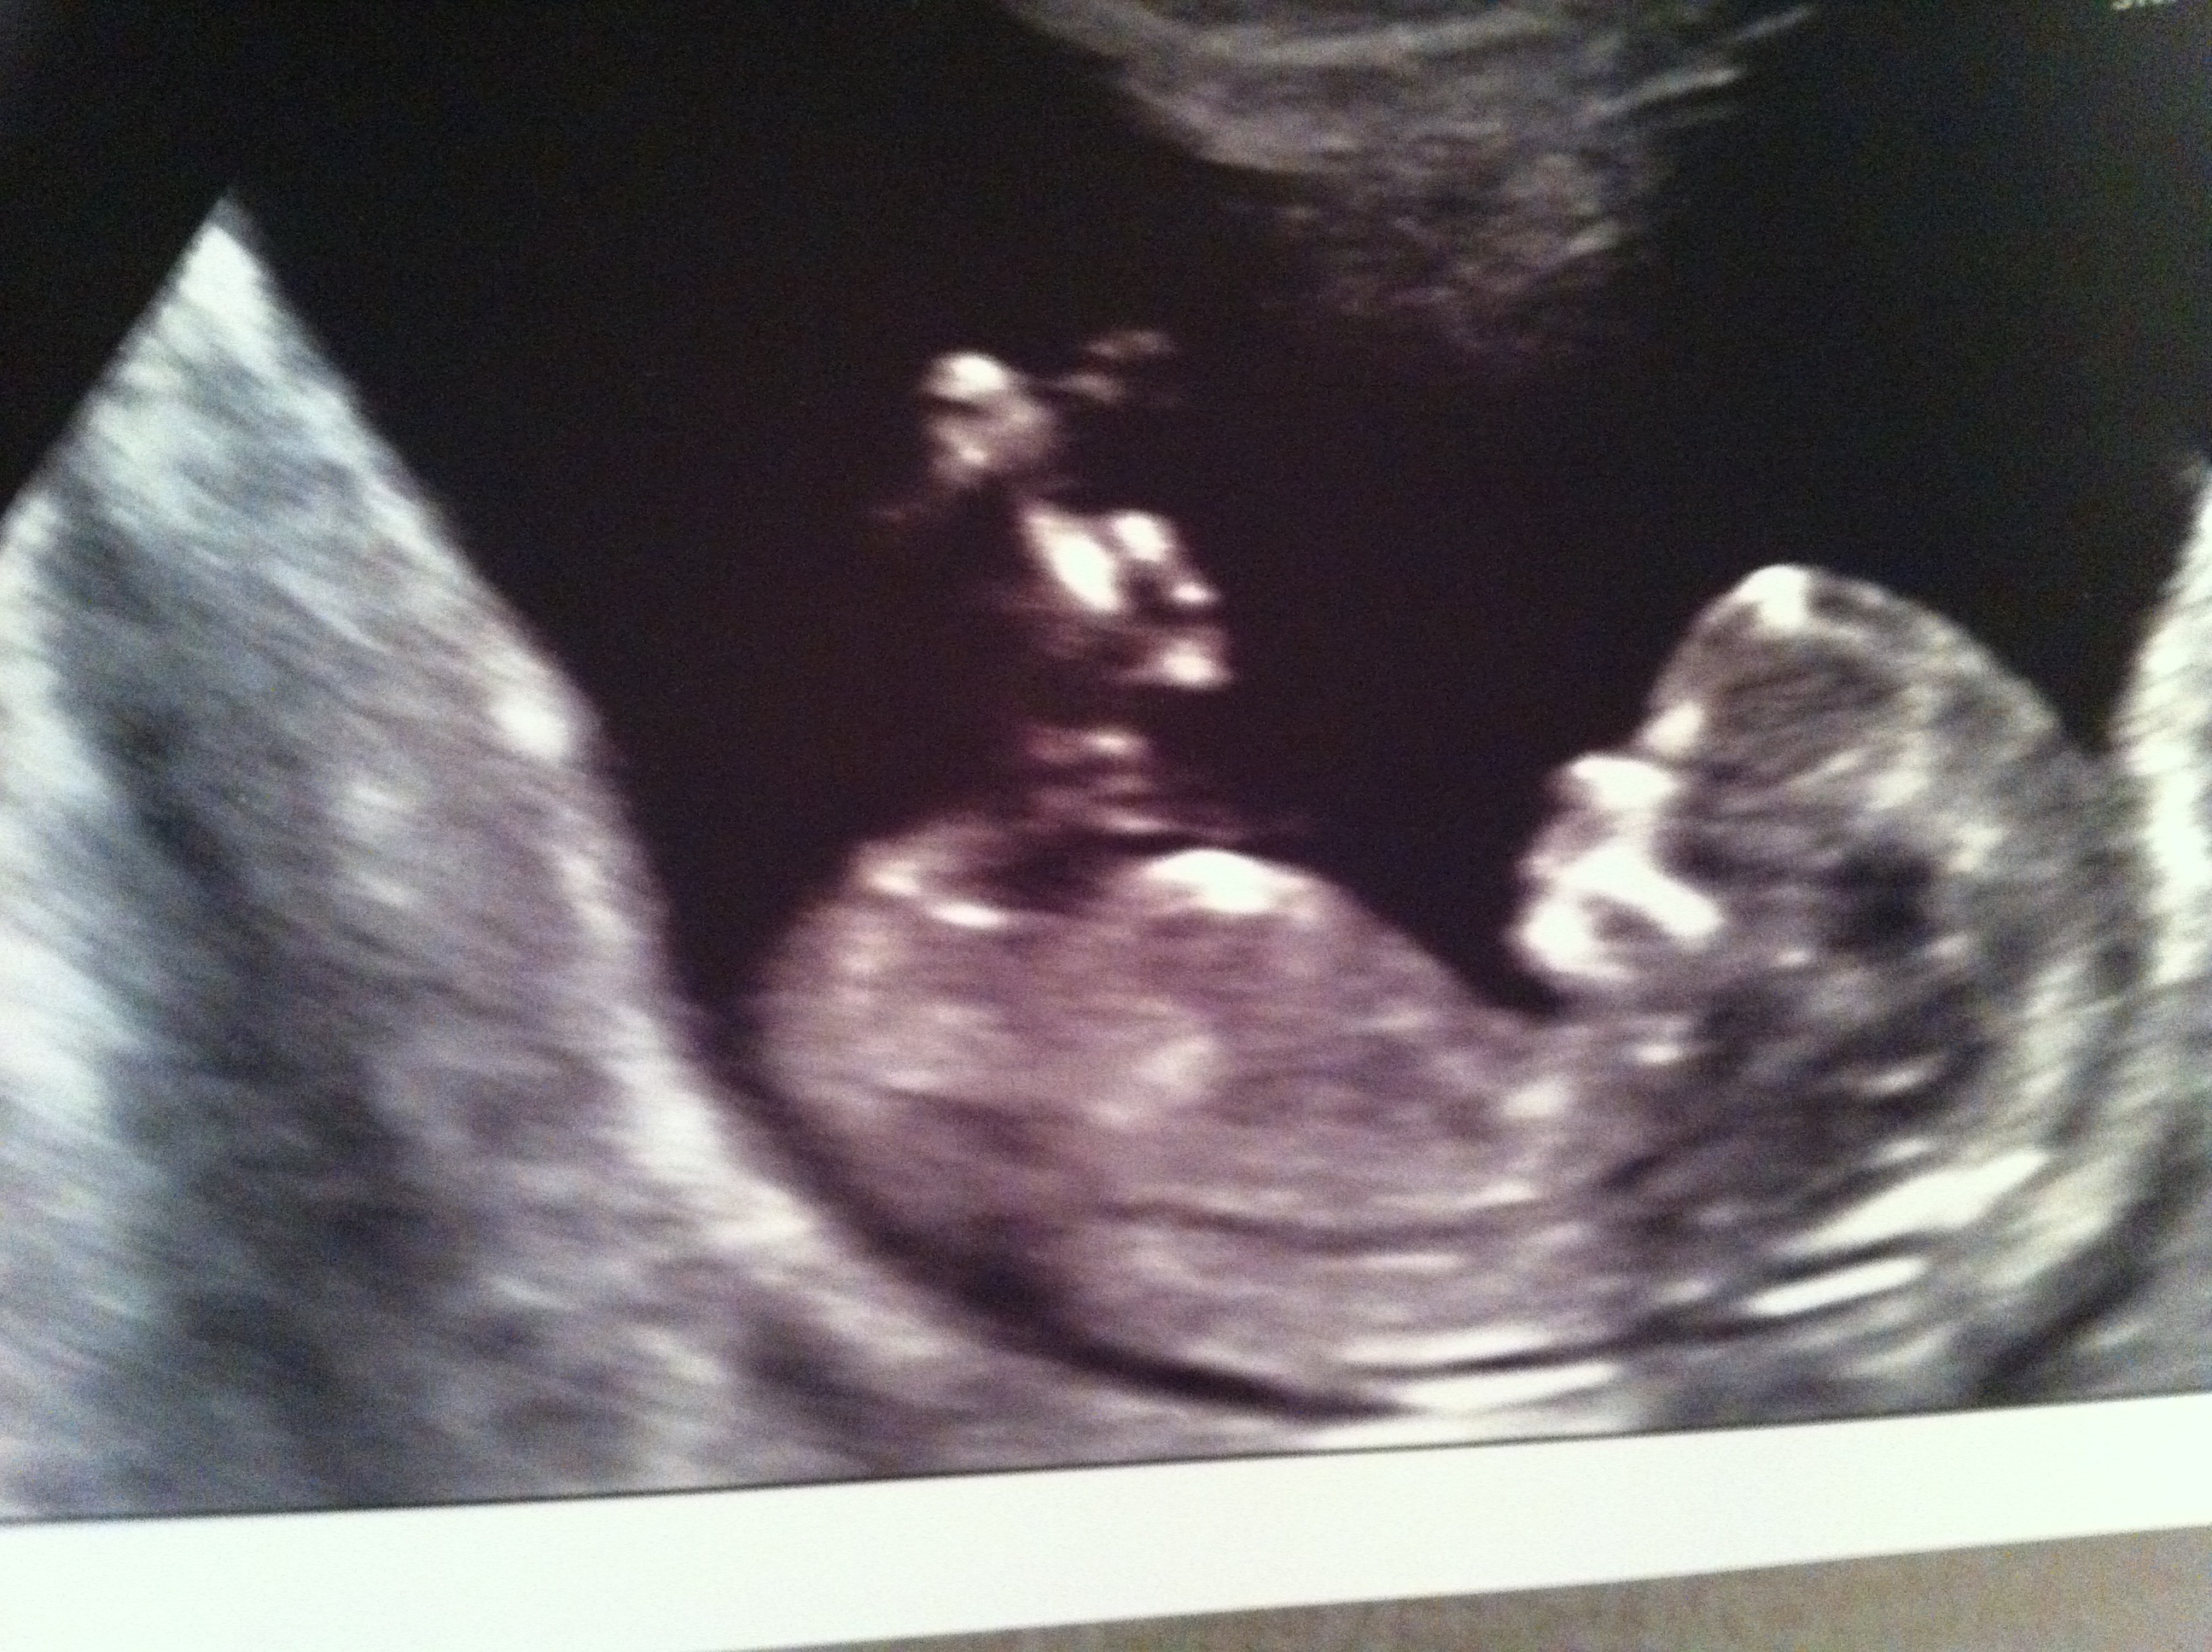

I don't think you can see a nub but if you do can you give me your best guess on nub and/or skull.

If that bright white line at the bottom is the nub I'd say girl since it appears parallel to the spine. I think the skull theory is 50/50 in all cases. What gestation?

I think girl but it's not the very best pic.

12w1d. Thank you for your responses